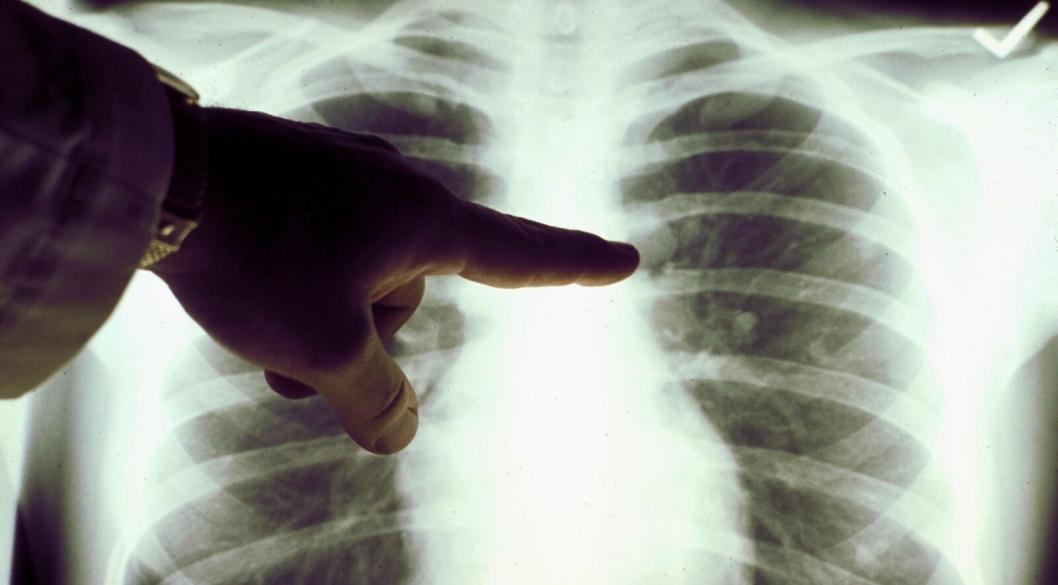

Изображение: департамент здравоохранения Тюменской области

В качестве ранней диагностики может выступить скрининг. Это ряд исследований, которые помогают выявить опухоль, пока она еще никаким образом себя не проявила. Так, можно пройти рентгенографию легких или компьютерную томографию, в том числе по полису ОМС в поликлинике по месту жительства. Желательно раз в год выполнять УЗИ брюшной полости и лимфоузлов, советует доктор.